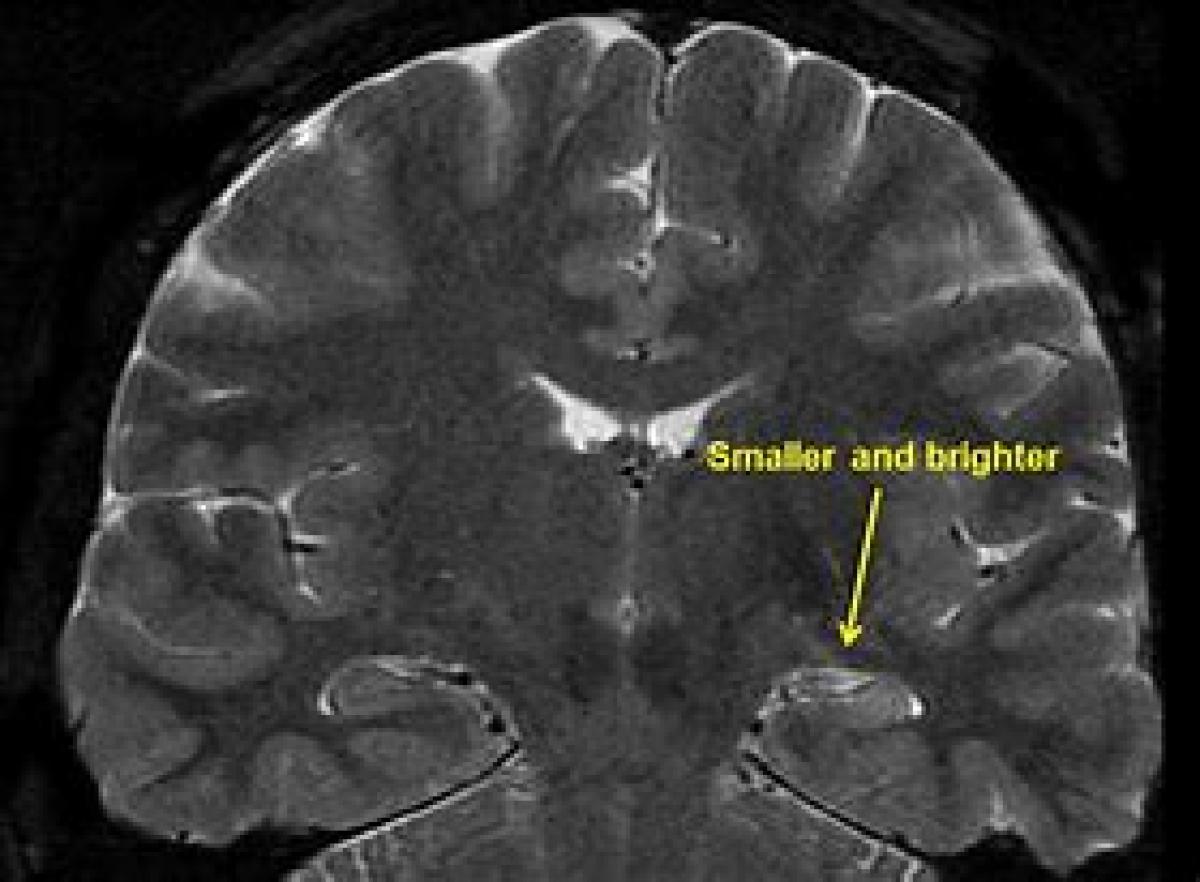

صرع لوب گیجگاهی معمولاً در دوران کودکی یا نوجوانی تشخیص داده می‌شود. این نوع صرع با بررسی پیشینه پزشکی، آزمایش خون و تصویربرداری مغزی و… تشخیص داده می‌شود. این بیماری می‌تواند دلایل مختلفی مانند آسیب به سر، سکته مغزی، عفونت‌های مغزی، ضایعات ساختاری در مغز یا تومورهای مغزی داشته‌باشد، یا می‌تواند دلایل ناشناخته دیگری نیز داشته‌باشد.